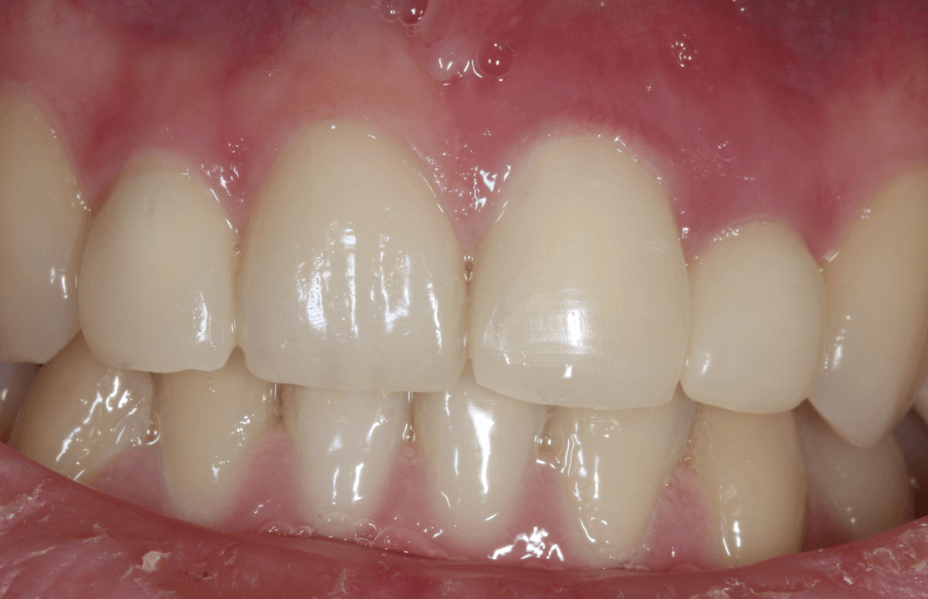

4. Próba

Többnyire egy bő hét alatt elkészül a korona vagy a híd, bár ez több időt is igénybe vehet. Mikor ez az idő letelt, jöhet a próba. Ha a korona vagy a híd tökéletesen illeszkedik, és a színe is megfelel a meglévő fogakénak, a fogtechnikusnak még egy-két napra szüksége lehet a véglegesítésre. Ha ez megvan, a koronát vagy hidat a helyére rögzítjük.

Bár szigorúan nem szükséges, szeretjük látni, hogyan működik a fogpótlás. Általában beragasztás után egy héttel, de legkésőbb akkor, amikor a páciens amúgy is eljön a félévente javasolt fogászati ellenőrzésre, megvizsgáljuk az újonnan kapott fogpótlását is.